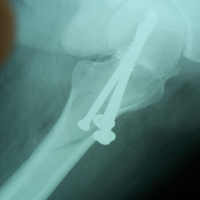

Case:7 Fracture Neck Femur with Implant failure and Re-Fixation with hemi-arthroplasty

Alcoholic Gardener by profession had slipped in bathroom & fell. He sustained fracture neck femur.He was operated with closed reduction & CC Screw fixation under IITV. Two weeks’ post fixation he again fell & sustained fracture in sub trochanteric region. He was treated with Hem-Arthroplasty with Tension band wiring.

Pre-Op

Post-Op

Post Fall

Oblique-Post Fall

Lat-Post Fall

Lateral-Post Prosthesis Fall

Post Prosthesis Fall

Post Uninon-3Months